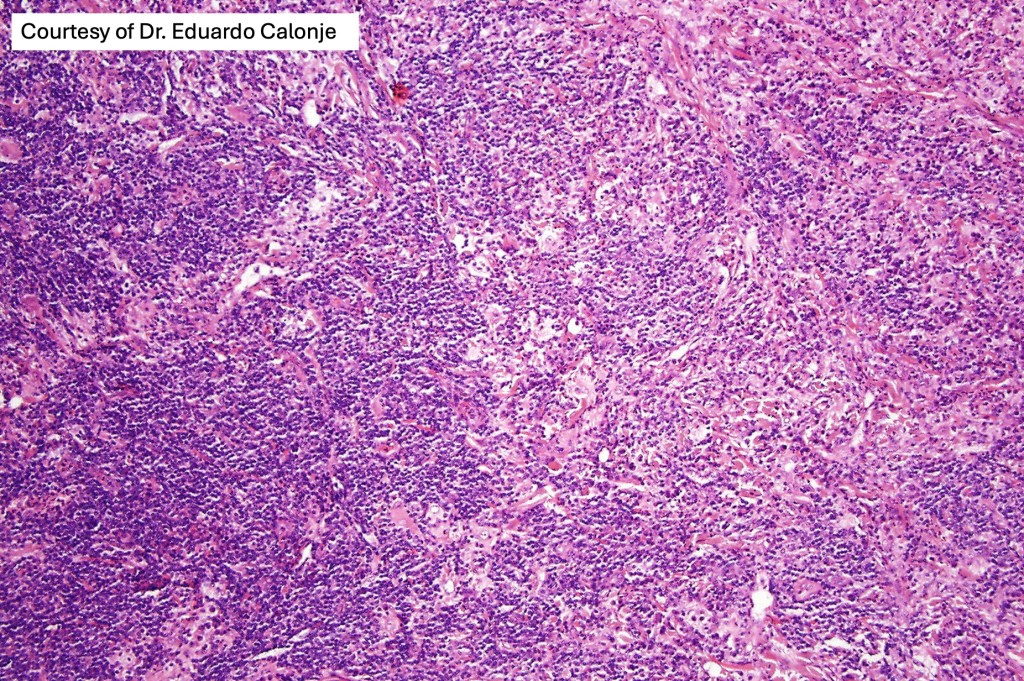

•Due to the admixture of pale histiocytes and lymphocytes, the scanning view is characteristic, and the diagnosis can be strongly suspected at this magnification

•Dense dermal nodular infiltrate sometimes extending into subcutaneous fat

•Background population of lymphocytes, plasma cells, neutrophils, eosinophils & variable numbers of xanthoma cells

•Lymphoid follicles with germinal centers sometimes present